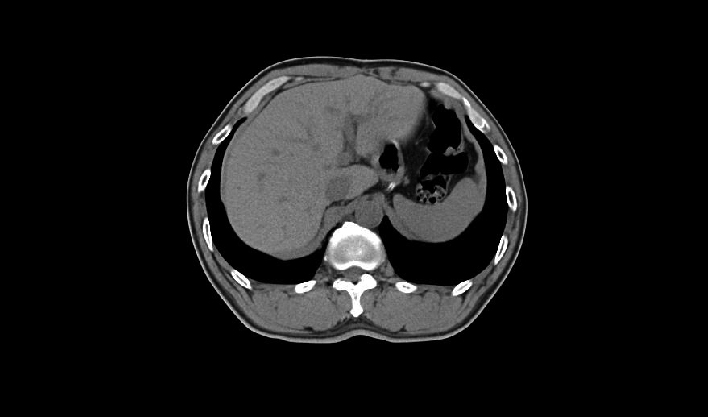

El detector de cuerpo ancho de cuarta generación, de desarrollo propio, cubre más áreas de tejido.

La matriz de reconstrucción de 1024*1024 amplía los datos de la imagen cuatro veces. Combinado con imágenes de corte fina, incluso las lesiones más invisibles son claramente visibles.